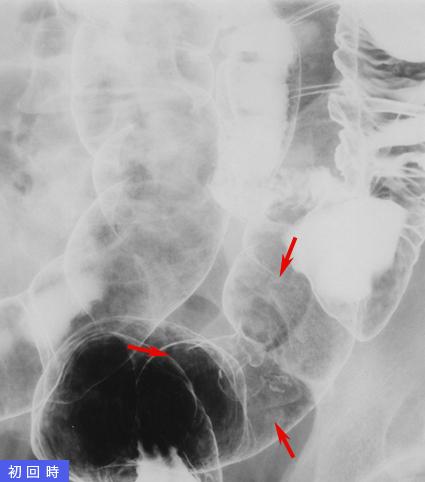

疾患(病理主体)の分類悪性上皮性腫瘍/その他

部位(臓器別)大腸/S状

検査方法X-P

腫瘍の肉眼分類0型(表在型)/IIa型(IIa+IIc)

病変の最大径(ミリ)15〜19

腫瘍の深達度sm